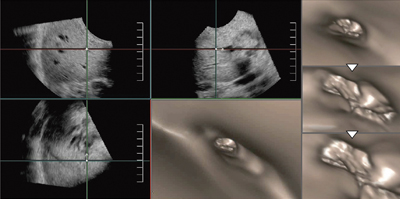

膵頭部がんによる閉塞性黄疸の症例(図2)では,膵頭部がんが大きいためERCPの挿管が困難で画像が得られなかったが,体表からの超音波によってFly Thruの3D画像を作成した。肝門部から乳頭側へ胆管内を視点移動し,狭窄,閉塞の状況が観察できたほか,胆管の表面性状は比較的平滑であることもわかった。

図2 膵頭部がんによる閉塞性黄疸のFly Thru画像

(肝門部→乳頭側へ)

ERCPにおける挿管困難例でも管腔の情報が得られる。